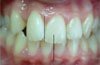

ORTA HAT UYUMSUZLUĞU

Üst orta hat ile alt orta hat uyumsuzdur. Arka bölgede kapanış bozukluğu mevcuttur. Fonksiyon ve estetik etkilenebilir.